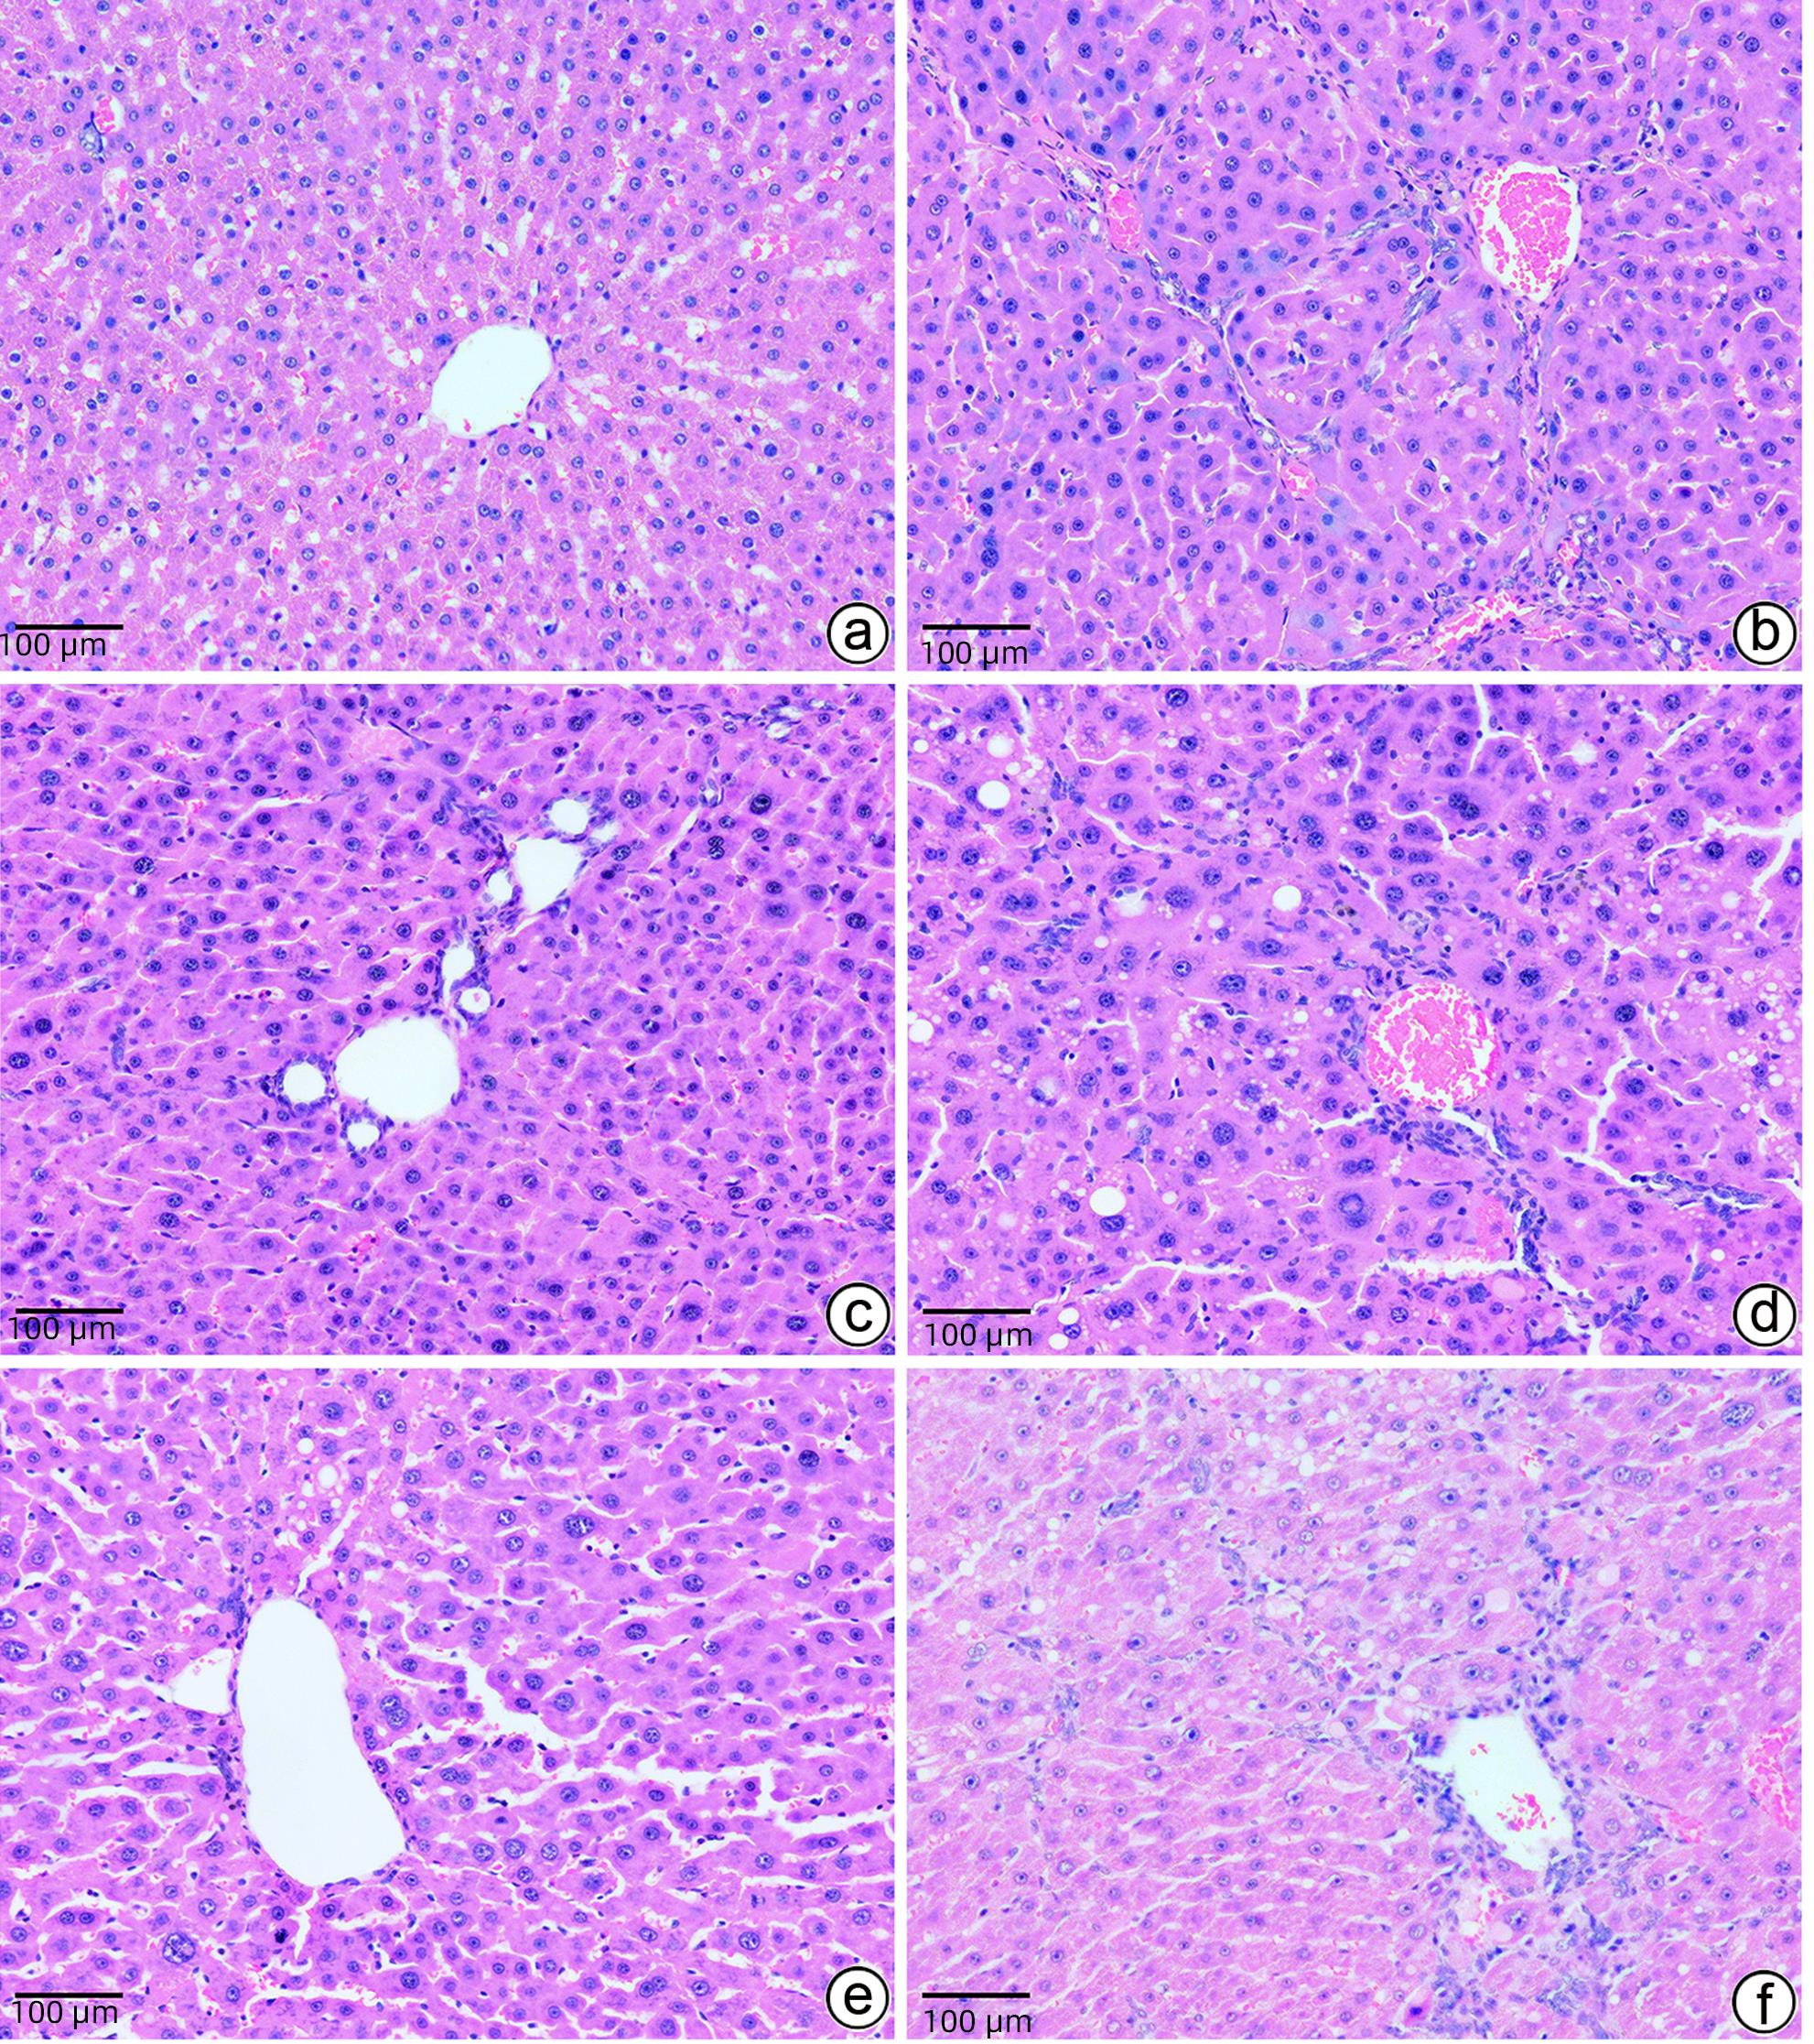

Objective  To investigate the role and possible mechanism of action of rhubarb decoction (RD) retention enema in improving inflammatory damage of brain tissue in a rat model of mild hepatic encephalopathy (MHE).  Methods  A total of 60 male Sprague-Dawley rats were divided into blank group (CON group with 6 rats) and chronic liver cirrhosis modeling group with 54 rats using the complete randomization method. After 12 weeks, 40 rats with successful modeling which were confirmed to meet the requirements for MHE model by the Morris water maze test were randomly divided into model group (MOD group), lactulose group (LT group), low-dose RD group (RD1 group), middle-dose RD group (RD2 group), and high-dose RD group (RD3 group), with 8 rats in each group. The rats in the CON group and the MOD group were given retention enema with 2 mL of normal saline once a day; the rats in the LT group were given retention enema with 2 mL of lactulose at a dose of 22.5% once a day; the rats in the RD1, RD2, and RD3 groups were given retention enema with 2 mL RD at a dose of 2.5, 5.0, and 7.5 g/kg, respectively, once a day. After 10 days of treatment, the Morris water maze test was performed to analyze the spatial learning and memory abilities of rats. The rats were analyzed from the following aspects: behavioral status; the serum levels of alanine aminotransferase (ALT), aspartate aminotransferase (AST), interleukin-1β (IL-1β), interleukin-6 (IL-6), and tumor necrosis factor-α (TNF-α) and the level of blood ammonia; pathological changes of liver tissue and brain tissue; the mRNA and protein expression levels of phosphatidylinositol 3-kinase (PI3K), protein kinase B (AKT), and mammalian target of rapamycin (mTOR) in brain tissue. A one-way analysis of variance was used for comparison of continuous data between multiple groups, and the least significant difference t-test was used for further comparison between two groups.  Results  Compared with the MOD group, the RD1, RD2, and RD3 groups had a significantly shorter escape latency (all P<0.01), significant reductions in the levels of ALT, AST, IL-1β, IL-6, TNF-α, and blood ammonia (all P<0.05), significant alleviation of the degeneration, necrosis, and inflammation of hepatocytes and brain cells, and significant reductions in the mRNA and protein expression levels of PI3K, AKT, and mTOR in brain tissue (all P<0.05), and the RD3 group had a better treatment outcome than the RD1 and RD2 groups.  Conclusion  Retention enema with RD can improve cognitive function and inflammatory damage of brain tissue in MHE rats, possibly by regulating the PI3K/AKT/mTOR signaling pathway.

Objective  To investigate the intervention mechanism of Dendrobium officinale leaf fermentation fluid in mice with alcoholic hepatitis.  Methods  A total of 70 healthy male C57BL/6J mice, aged 6-8 weeks, were randomly divided into normal group, model group, liquid feed control group, silybin group, and low-, middle-, and high-dose Dendrobium officinale leaf fermentation fluid groups, with 10 mice in each group. The mice in the normal group were given normal diet, and those in the other groups were given Lieber-DeCarli classic liquid diet for 8 weeks to induce alcoholic hepatitis. During modeling, the mice in the low-, middle-, and high-dose Dendrobium officinale leaf fermentation fluid groups were given Dendrobium liquid manufactured by Warmen Pharmaceutical, and the mice in all the other groups were given pure water; the mice in the normal group, the model group, and the liquid feed control group were given normal saline by gavage, those in the silybin group were given silybin 0.25 mL/10 g by gavage, and those in the low-, middle-, and high-dose Dendrobium officinale leaf fermentation fluid groups were given Dendrobium officinale leaf fermentation fluid at a dose of 0.125 mL/10 g, 0.250 mL/10 g, and 0.375 mL/10 g, respectively, by gavage, once a day. At week 8, chloral hydrate was injected intraperitoneally for anesthesia, and blood samples were collected from the eyeball. After serum was separated, the biochemical method was used to measure the levels of aspartate aminotransferase (AST) and alanine aminotransferase (ALT); HE staining and oil red staining were used to observe liver histopathology and lipid accumulation in mice; multiplex Luminex assay was used to measure the serum levels of interleukin-6 (IL-6), interleukin-1β (IL-1β), tumor necrosis factor-α (TNF-α), and CCL2; quantitative real-time PCR, Western blot, and immunofluorescence assay were used to measure the protein expression levels of NLRP3, caspase-1, caspase-11, gasdermin D (GSDMD), N-terminal gasdermin D (GSDMD-N) in liver tissue. A one-way analysis of variance was used for comparison of continuous data between multiple groups, and the least significant difference t-test was used for further comparison between two groups.  Results  Compared with the normal group, the model group had significant increases in the serum levels of AST, ALT, IL-6, IL-1β, TNF-α, and CCL2 (all P<0.05), and compared with the model group, the high-dose Dendrobium officinale leaf fermentation fluid group had significant reductions in the serum levels of AST, ALT, IL-6, IL-1β, TNF-α, and CCL2 (all P<0.05). HE staining showed that the model group had disordered structure of hepatic lobules, with a large number of steatosis vacuoles and massive cell necrosis, and compared with the model group, the high-dose Dendrobium officinale leaf fermentation fluid group had alleviation of liver histopathological injury, intact structure of most hepatic lobules, and a small amount of inflammatory cell infiltration. Oil red staining showed that the model group had accumulation of large and small lipid droplets in the liver and a significant increase in liver fat content, and compared with the model group, the high-dose Dendrobium officinale leaf fermentation fluid group had significant alleviation of hepatic steatosis, with the presence of sporadic small lipid droplets. Immunofluorescence assay of liver tissue showed that compared with the normal group, the model group had a significant increase in the ratio of GSDMD-positive staining area in hepatocyte cytoplasm (P<0.001), and compared with the model group, the high-dose Dendrobium officinale leaf fermentation fluid group had a significant reduction in such ratio in hepatocyte cytoplasm (P<0.001). Quantitative real-time PCR showed that compared with the normal group, the model group had significant increases in the protein expression levels of NLRP3, caspase-1, caspase-11, GSDMD, GSDMD-N, interleukin-18 (IL-18), and IL-1β in liver tissue (all P<0.05), and compared with the model group, the high-dose Dendrobium officinale leaf fermentation fluid group had significant reductions in the protein expression levels of NLRP3, caspase-1, caspase-11, GSDMD, GSDMD-N, IL-18, and IL-1 (all P<0.05). Compared with the model group, the high-dose Dendrobium officinale leaf fermentation fluid group had significant reductions in the protein expression levels of caspase-1 and caspase-11 (both P<0.05), with a relative expression level of caspase-1 of 1.757 (reduced by 26.6% compared with the model group) and a relative expression level of caspase-11 of 0.455 (reduced by 70.3% compared with the model group), suggesting that caspase-11 showed a greater reduction than caspase-1.  Conclusion  Dendrobium officinale leaf fermentation fluid can alleviate alcoholic hepatitis in mice, possibly by inhibiting the non-classical cell pyroptosis pathway mediated by caspase-11.